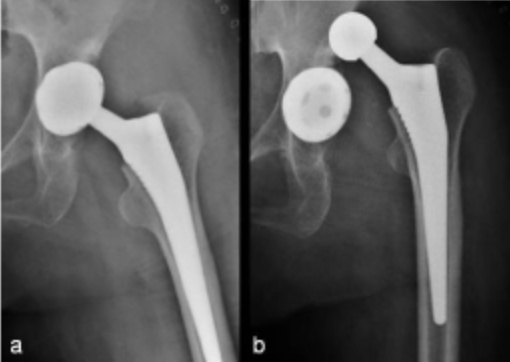

직접 전방 접근법을 이용한 고관절 전치환술.

이러한 변화는 약물의 사용과 빠른 회복 프로토콜이라는 수술 전후 관리 프로그램의 개발로 가능했지만 가장 큰 변화는 고관절 전치환술에 소위 “최소 침습 수술”이라는 개념을 도입한 것입니다. . . 구체적으로 “최소침습 고관절 치환술”의 진정한 의미는 “직접 전방 도달을 통한 고관절 전치환술”그것이 대중화되었습니다.

직접 전방 접근 수술은 19세기 오스트리아 의사 Heuter에 의해 처음 소개되었고, 미국 의사 Smith-Peterson과 프랑스 의사 Judet은 이 방법을 고관절 치환술에 현대적인 방법으로 도입했습니다.

이 때문에 전통적으로 많은 고관절 전문의들이 사용하는 ‘후방 도달법’, ‘측면 도달법’ 등 이른바 인공 고관절 수술법보다 ‘직접 전방 도달법’이 조금 더 까다롭다. , 환자 만족도가 높고 합병증이 좋습니다.

1. 최소 침습: 직접 전방 접근법은 관절에 접근하기 위해 골반 앞쪽에 작은 절개를 사용하는 최소 침습 절차인 반면, 전통적인 고관절 교체 수술은 일반적으로 더 큰 절개가 필요합니다. 이것은 통증, 출혈 및 흉터를 줄일 수 있습니다.

2. 근육 보존: 기존의 수술 방법과 달리 큰 근육을 절단할 필요가 없으므로 회복 시간이 빠르고 기능적 결과가 더 좋습니다.

3. 탈구 위험 감소 : 큰 근육을 절단할 필요가 없기 때문에 탈구 위험이 감소합니다.

4. 더 빠른 회복: 최소 침습 특성과 근육 보존 기술로 인해 환자는 더 빨리 회복하고 더 빨리 정상적인 활동으로 돌아갈 수 있습니다.

5. 수술 정확도 향상 : 직접전방접근법은 수술 중 영상을 통해 식립 과정을 용이하게 하기 때문에 수술 시 정확도와 정밀도를 높여 더 나은 결과를 얻을 수 있습니다.